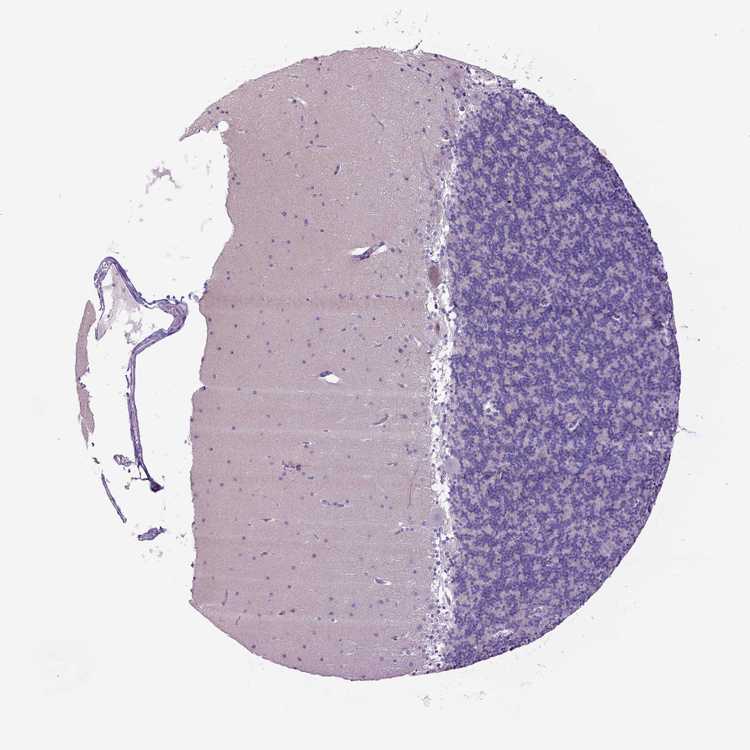

CEREBELLUM - Antibody stainingi

Antibody staining in the annotated cell types in the current human tissue is reported as not detected, low, medium, or high, based on conventional immunohistochemistry profiling in selected tissues. This score is based on the combination of the staining intensity and fraction of stained cells.

Each image is clickable and will lead to virtual microscopy that enables deeper exploration of all samples and also displays staining intensity scores, fraction scores and subcellular localization as well as patient and tissue information for each sample.

Antibody CAB033645

Purkinje cells Not detected

Cells in granular layer Not detected

Cells in molecular layer Not detected